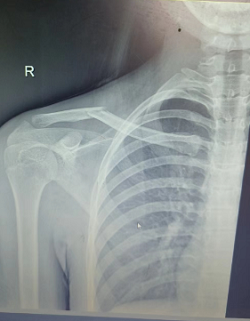

15岁的小周是一个成绩非常优秀的女孩子,一次意外后出现锁骨骨折。锁骨骨折了那怎么办?这可愁坏了父母!要是按照传统治疗那就这样:手术切口像个“蜈蚣”样,影响了美观。小周父母实在是发愁,到处打听,了解到了我院骨科可以进行微创手术治疗,切口小,恢复快,于是将孩子带到我院就医。我院骨科丁晔医师查看后,对患者采取微创闭合复位经皮弹性髓内钉内固定术。手术属于微创手术,仅需0.5cm的小切口从锁骨远端或锁骨近端为进针点...